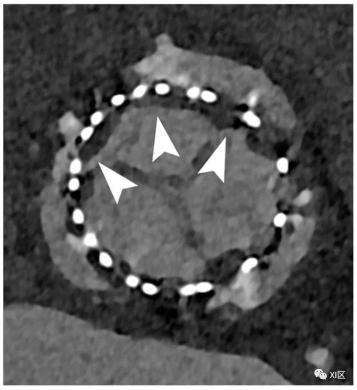

主动脉瓣假体的心脏PCCT。在这个示例中,我们展示了主动脉瓣人工瓣膜的随访情况,该人工瓣膜显示出明显的瓣叶低度增厚(HALT)迹象,这可能是由于血栓附着(箭头),并可能影响瓣叶运动。使用PCCT可以很容易地看到这层非常薄的低密度组织。